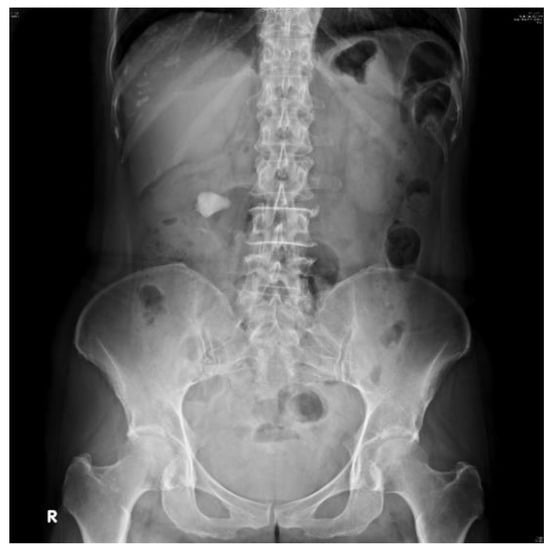

2.3. Image Preprocessing

2.3.1. Contrast-Limited Adaptive Histogram Equalization

2.3.2. Image Mask

2.3.3. Image Cropping